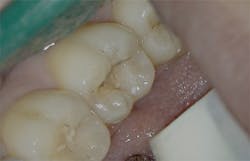

Figure 3: Class I cavity prep after laser. Photo courtesy of Jeff Rhode, DDS.

For the same reasons, the 10.6-micron CO2 laser has also been shown to damage the implant surface and increase the temperature of the adjacent hard and soft tissue surrounding the dental implant.4 Because of the difference in wavelength, absorption pattern, and introduction of water irrigation with the 9.3-micron CO2 laser (figure 1), it can now be used for hard-tissue applications. This laser has been used to prepare teeth for Class I–IV (figures 2–8) restorations without the concern of raising pulpal temperature and inducing necrosis. The laser has also been used as an alternative to conventional high-speed drills to prepare teeth for crowns, bridges, and veneers.